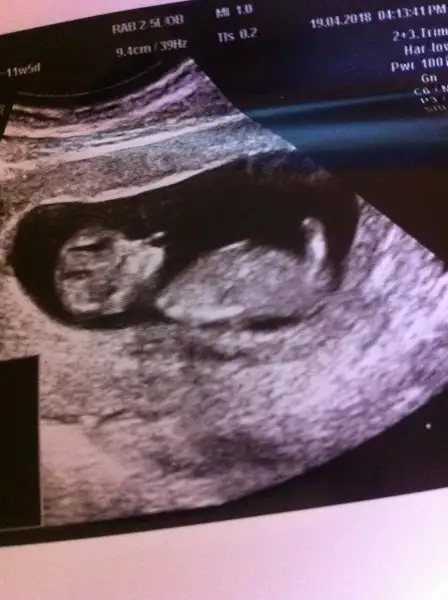

Günaydın anneler dün 2li tarama testi için hastanedeydik 11+5 di Adet tarihime göre ama doktor 12+3 ölçtü 5 gün ilerde gidiyor bebeğinin gelişimi çok güzel dedi çok şükür ense kalınlığı da ölçüldü ölçümlernde hiçbir problem görülmedi rabbime şükür ama cinsiyet konusunda 2 tane doktora girdik biri ultrasoncu biri kendi doktorum ikiside çok ketun çıktı bir tahminde bulunmak istemediler bende sizlerden rica ediyorum yorumlarmısınızz. İlgilenen herkese teşekkür ederim

Eklentiler

• image.webp

19,5 KB · Görüntüleme: 111

• image (1).webp

17,2 KB · Görüntüleme: 104